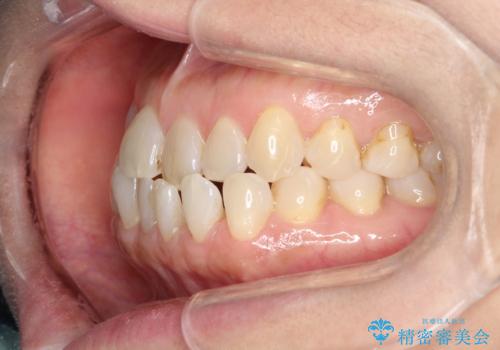

前歯の隙間 インビザラインによる目立たない成人矯正

- 前歯の隙間を気にされて来院されました。

インビザラインにて、目立たずに矯正治療を行うこととしました。

歯と歯の間にある隙間を閉じるのは、インビザラインでもしっかり治療できます。